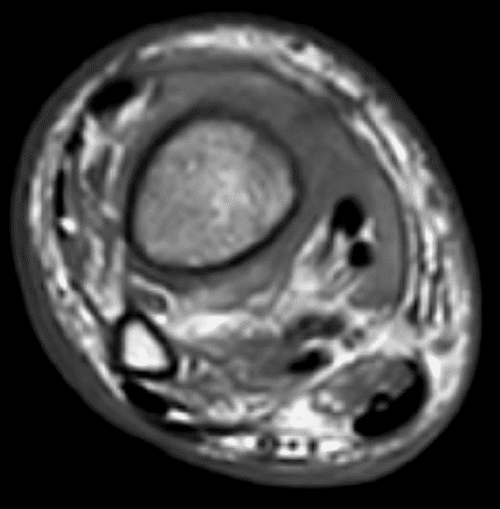

Magnetic resonance imaging (MRI) of the right lower extremity showed findings consistent with noninfectious osteomyelitis—diffuse soft tissue edema around the right ankle with effusion, fluid in the posterior tibialis tendon sheath with synovial and muscle enhancement, and osseous hyperenhancement of the mid-tibial shaft with periosteal edema (Figure 2). Computerized tomography (CT) scan of the abdomen and pelvis with IV contrast was notable for soft tissue stranding around the pancreatic head, a large pancreatolith in the body of the pancreas, and a non-occlusive superior mesenteric vein (SMV) thrombus (Figure 3). MRI of the abdomen demonstrated pancreatic ductal dilation and a focal area of pancreatic necrosis in the uncinate directly adjacent to the SMV (Figure 4).

Figure 2. CT Scans. Published with Permission

A.

A) Axial T1 MRI

B.

B) axial T2 fat-suppressed MRI through the distal lower leg showing bone marrow edema in the tibia but not the fibula, soft tissue edema surrounding the tibia, and periosteal new bone along the lateral aspect of the tibia

C.

C) Coronal STIR MRI showing distal tibial bone marrow edema and extensive intramuscular and subcutaneous edema

D.

D) Sagittal T1 fat-suppressed gadolinium-enhanced MRI showing heterogeneous distal tibial bone marrow enhancement and diffuse intramuscular enhancement